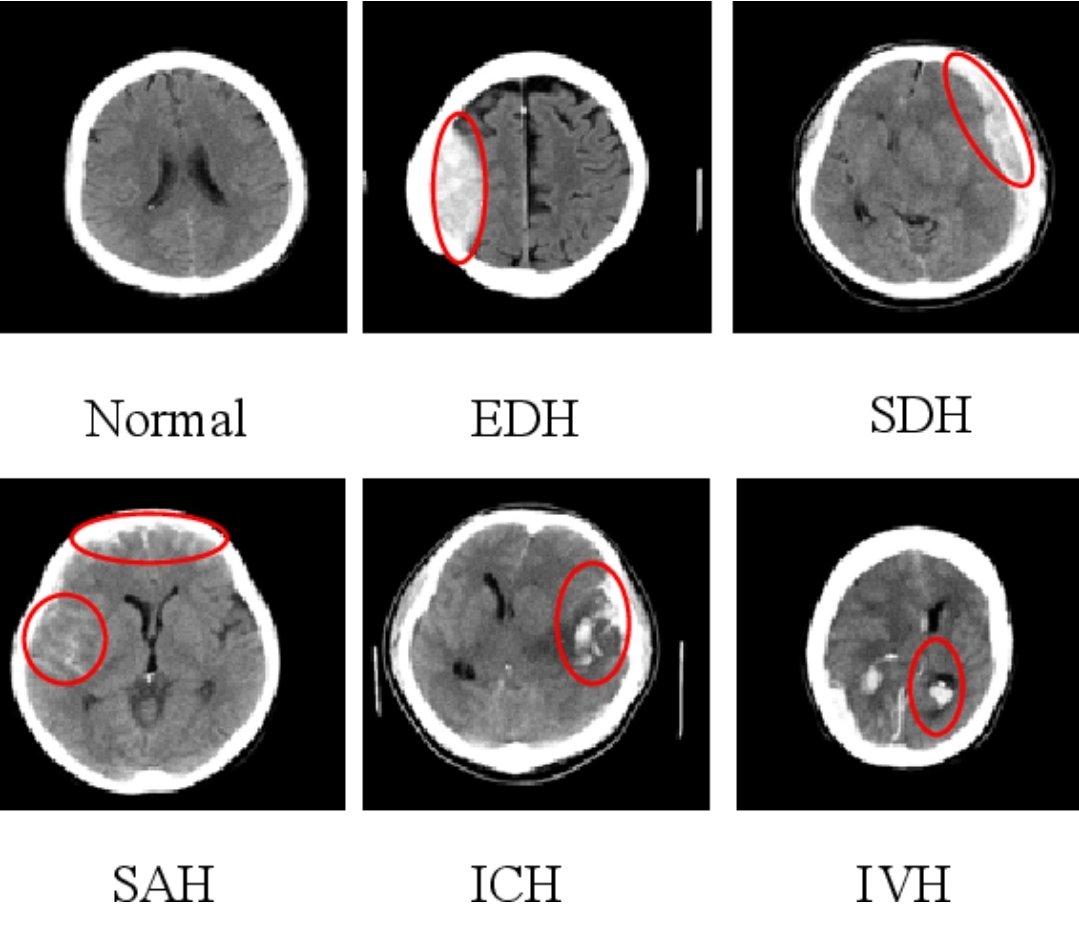

💥الفحوصات

🧠تحاليل دم

🧠اشعه مقطعيه للمخ

🧠اشعه بالصبغه

🧠اشعه تداخليه بالقسطرة للتشخيص والعلاج

💥الفحوصات

🧠تحاليل دم

🧠اشعه مقطعيه للمخ

🧠اشعه بالصبغه

🧠اشعه تداخليه بالقسطرة للتشخيص والعلاج

💥الفحوصات الاساسيه

🧠اشعه مقطعيه/رنين للمخ

🧠دراسه الشرايين المغذيه للمخ

تختار حسب مكان الجلطه/وظائف الكلى/التوفر

(مقطعيه بالصبغه/رنين مغناطيسي/اشعه صوتيه للرقبه/قسطرة تداخليه)

💥الفحوصات الاساسيه

🧠اشعه مقطعيه/رنين للمخ

🧠دراسه الشرايين المغذيه للمخ

تختار حسب مكان الجلطه/وظائف الكلى/التوفر

(مقطعيه بالصبغه/رنين مغناطيسي/اشعه صوتيه للرقبه/قسطرة تداخليه)